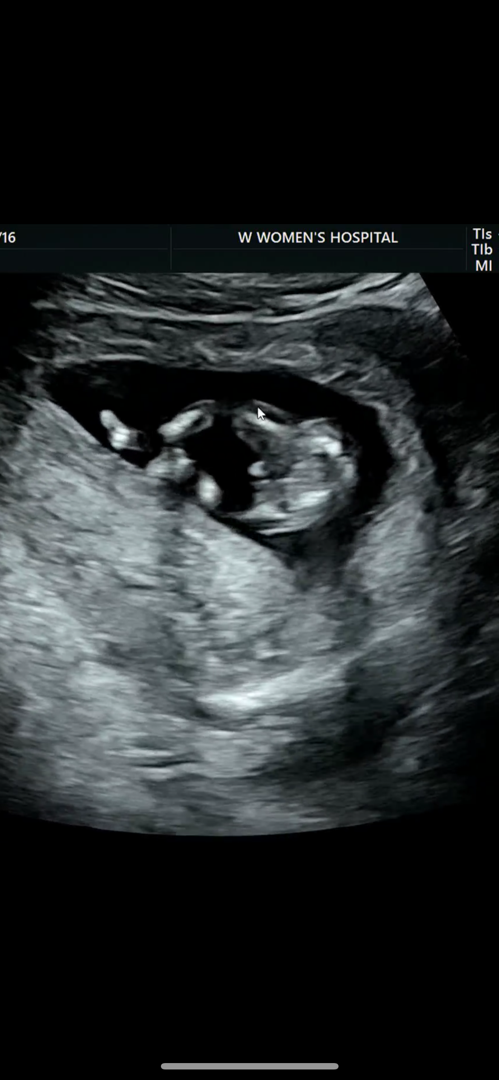

12주6일차 아가 성별 질문!

밑에서 찍은 사진인데요 아들인가요 ? 주차 지나면 없어지기도 하나요?

저정도면 아들같은데 결과 궁금하네요 ㅋㅋㅋ

존재감이 강하네요~~하하

없어지면 딸 커지면 아들이래요~ 13주 14주까진 가야 확실하대요~